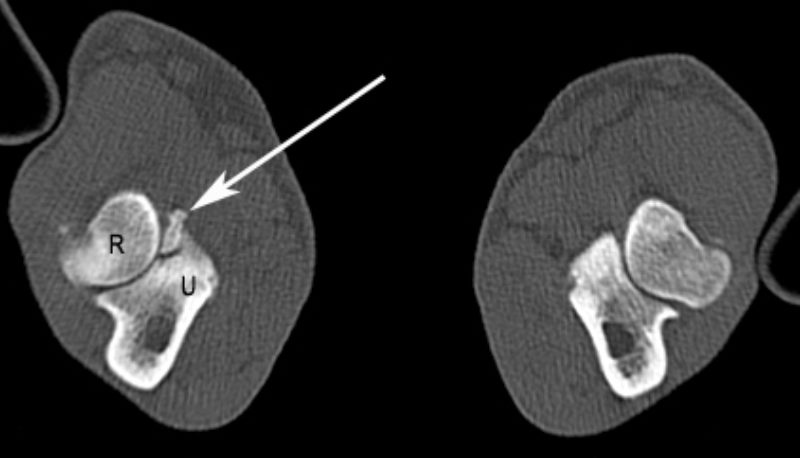

Nachdem ich bei „Oscar“ die Narkosefähigkeit geprüft hatte, haben wir einen Venenkatheter eingelegt und darüber die Narkose eingeleitet. „Oscar“ bekam einen Luftröhrentubus, damit in der Narkose die Atmung nicht behindert wird und er Narkosegase einatmen kann. „Oscar“ wurde für die Untersuchung der Ellbogengelenke in Brustlage mit gestreckten Vordergliedmaßen auf dem Untersuchungstisch gelagert und mit kontrastarmen Lagerungshilfen (z.B. Schaumstoffkeile oder Rohrisolationen) positioniert. Die reine Untersuchungszeit im CT beträgt für eine Ellbogensequenz ca. 10-15 Sekunden (120 kV, 200 mAs, Schichtdicke 0,75 mm, W 2500 L 500, Ellbogen beidseits transversal, nativ). Bei „Oscar“ fand ich auf diese Weise einen feinen Riss am inneren Kronfortsatz der Elle (Processus coronoideus medialis ulnae). Seine eigentliche Spitze war durch Entmineralisation bereits weniger röntgendicht. Als Folge dieses „Bruches“ war es zu einer Reizung des Gelenks und damit zu einer beginnenden Arthrose mit Ausbildung von Knochenspikes gekommen.

Somit stand die Diagnose „abgebrochener innerer Kronfortsatz“ (fragmentierter Processus coronoideus medialis ulnae) als Ursache für die Lahmheit bei „Oscar“ fest. Diese Erkrankung zählt zum Formenkreis der Ellbogengelenkdysplasie und ist eine der häufigsten Lahmheitsursachen der Vordergliedmaße beim großwüchsigen Hund. Da das Belassen des abgebrochenen Kronfortsatzes die Arthrosebildung begünstigt, haben wir in der gleichen Narkose das Bruchstück arthroskopisch entfernt.